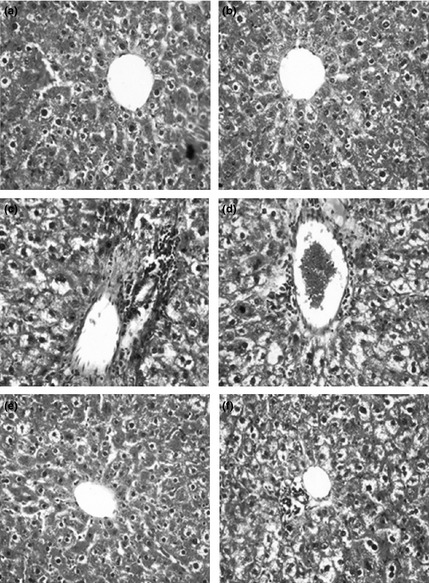

Figure 4 depicts photomicrographs of H&E‐stained liver sections of the control and experimental rats. Livers of control and d‐carvone‐alone‐exposed rats had normal liver architecture (groups I and II). Animals exposed to DMH alone (group III) had changes in the liver characterized by micro and macro vesicular type of fatty changes, Kupffer cell hyperplasia, nuclear pleomorphism and inflammatory cell infiltration in the portal triad (4c). Livers of DMH + d‐carvone (5 mg/kg body weight) (group IV)‐supplemented rats had marked inflammatory cell infiltrates around the portal triad and also neoplastic cells (4d). Livers of DMH + d‐carvone (10 mg/kg body weight) (group V) rats showed near normal architecture (4e) and livers of DMH + d‐carvone (20 mg/kg body weight) (group VI)‐supplemented rats had fewer neoplastic cells (4f).

Figure 4.

Histopathological findings in the liver of control and experimental rats [H&E staining]. (a and b) Liver of control and control + d‐carvone (20 mg/kg body weight)‐supplemented rats showing normal liver architecture with central portal vein. 1,2‐Dimethylhydrazine (DMH)‐alone‐exposed rat liver (group III) showing micro and macrovesicular type of fatty changes, Kupffer cell hyperplasia, nuclear pleomorphism and inflammatory cell infiltrates in the portal triad (c). The liver section of DMH + d‐carvone 5 mg/kg body weight (group IV)‐supplemented rat showing marked inflammatory cell infiltrates and neoplastic cells around the portal triad (d). The liver of DMH + d‐carvone 10 mg/kg body weight (group V) showing near normal architecture (e). The liver of DMH + d‐carvone 20 mg/kg body weight (group VI)‐supplemented rat showing less neoplastic cells and near normal architecture (f).

Furthermore, our histopathological observations reveal that DMH induction produced a range of pathological abnormalities in the liver and colon. Liver histology of DMH‐alone‐exposed rats showed marked pathological alterations such as fatty change, Kupffer cell hyperplasia, nuclear pleomorphism and inflammatory cell infiltrate in the portal triad. DMH‐induced rat colonic tissue showed loss of epithelial integrity, dilated lumina, lymphoid aggregates and intense infiltration of inflammatory cells into the mucosal layer. However, oral supplementation with d‐carvone to DMH‐exposed rats reduced pathological alterations in the liver and colon validating d‐carvone as a promising anti‐carcinogenic and hepatoprotective agent during colon carcinogenesis.